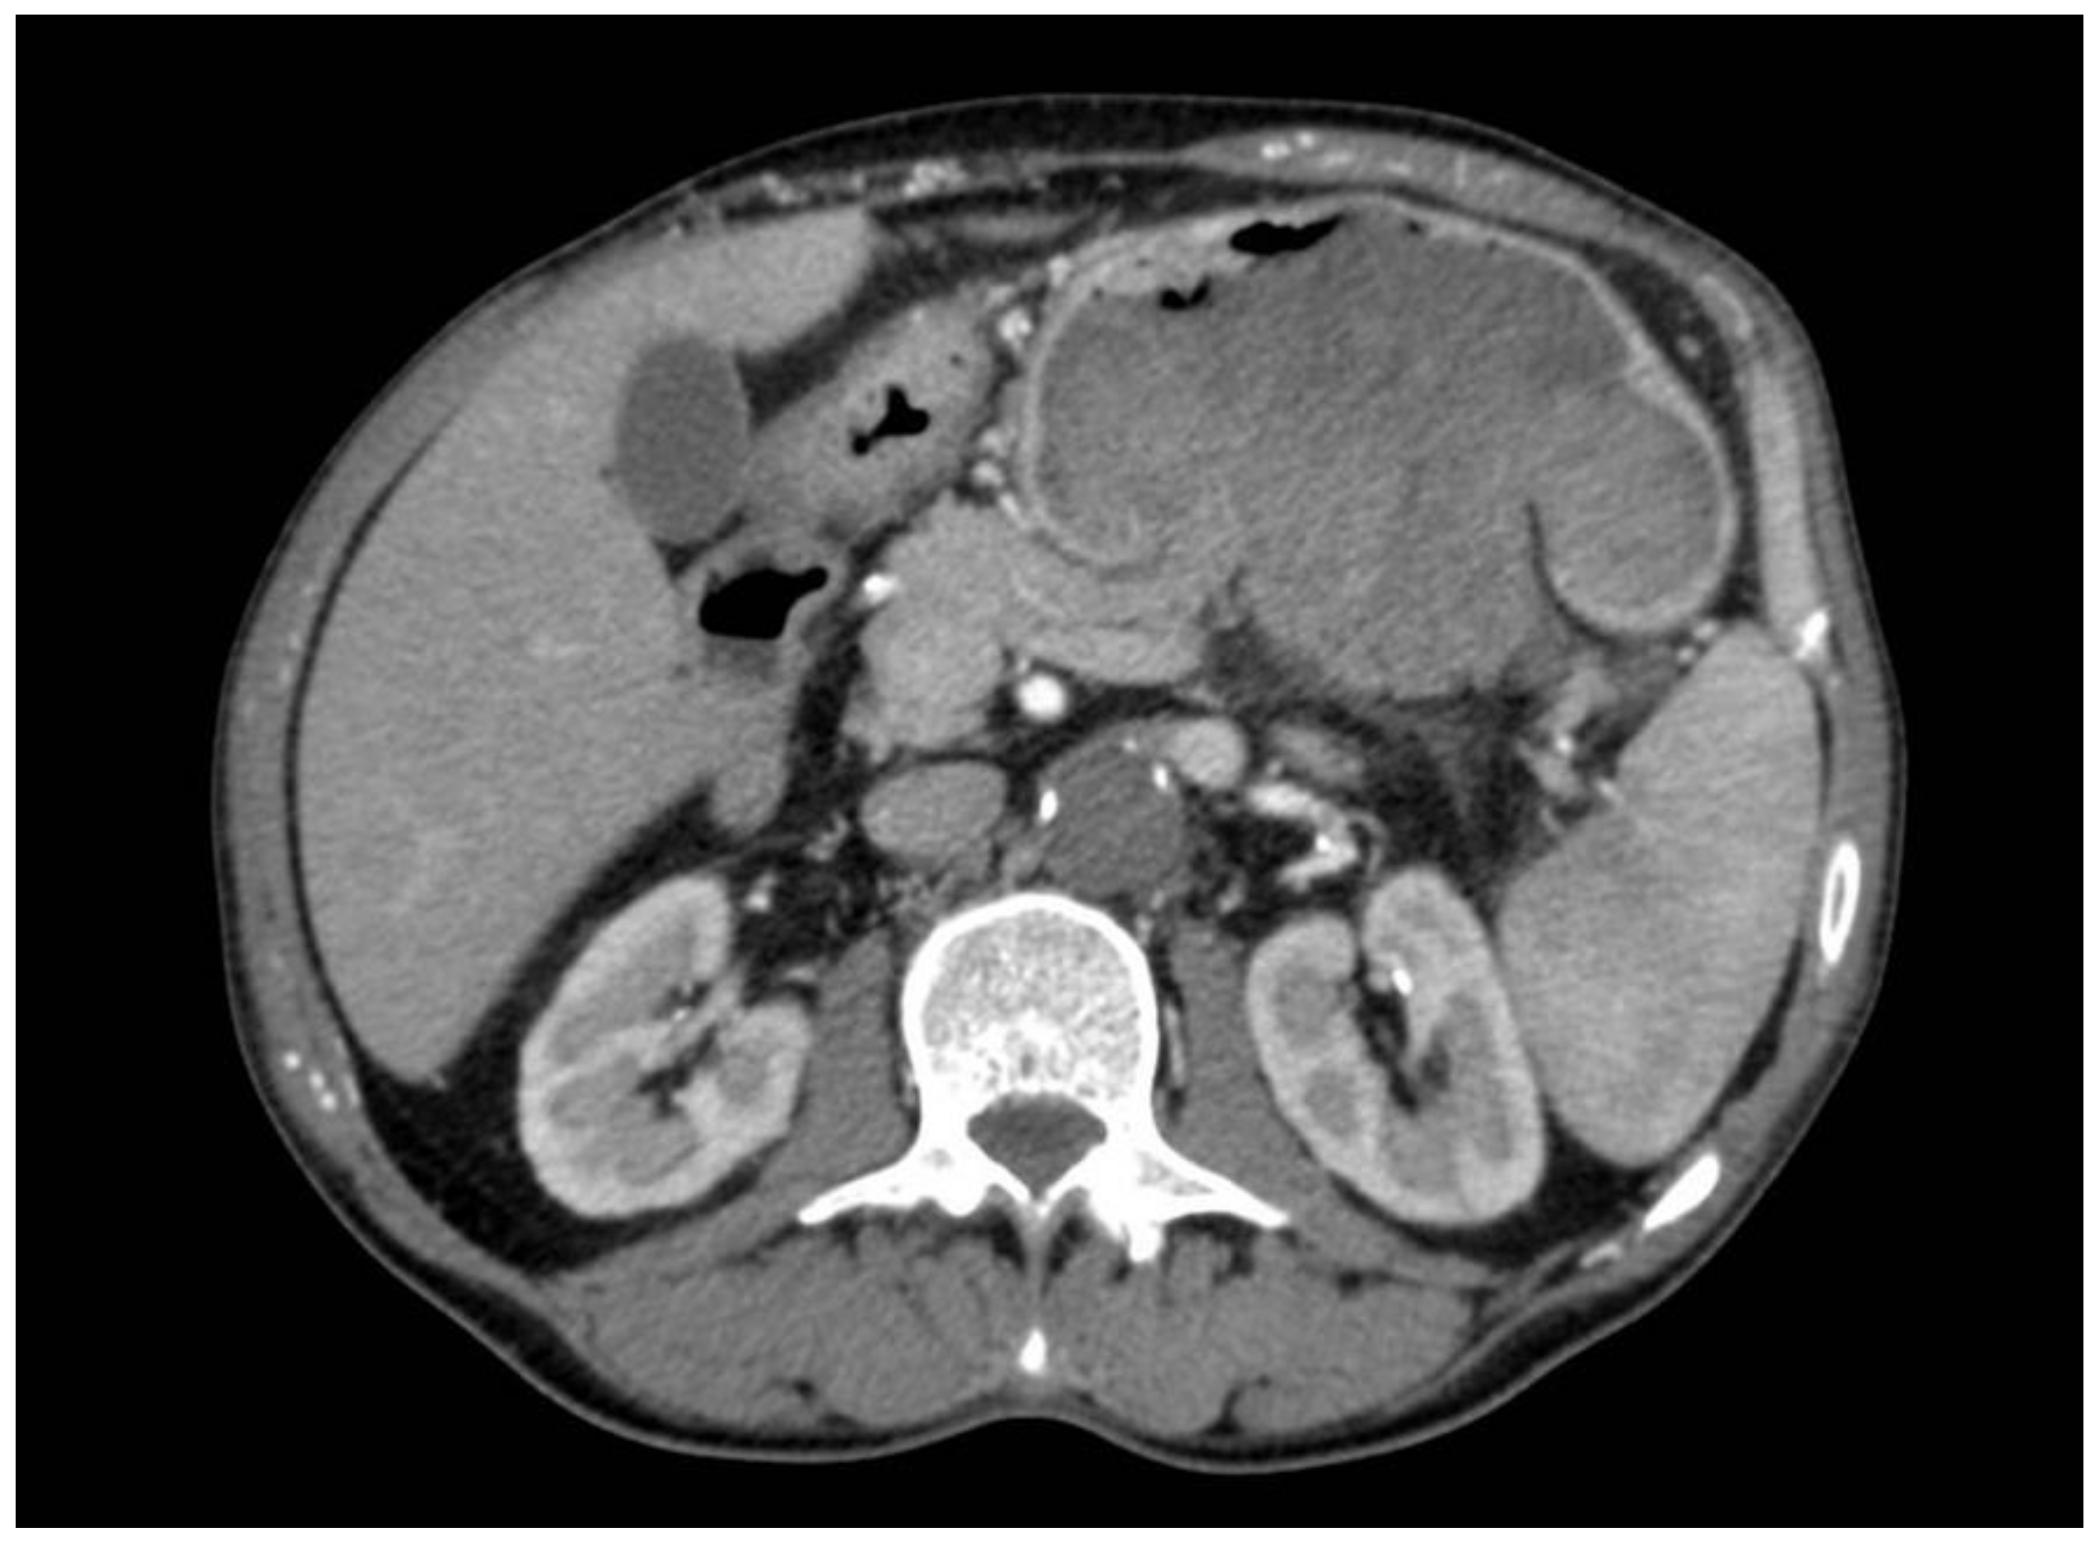

2. Case Report